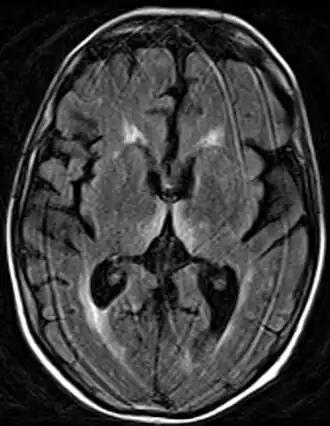

Lesão no diencéfalo, especificamente no núcleo dorsomedial do tálamo e nos corpos mamilares.

A síndrome de Korsakoff é atribuída a uma lesão no diencéfalo, especificamente no núcleo dorsomedial do tálamo e nos corpos mamilares, que, como vistos, são essenciais na construção da memória, o que causaria a amnésia anterógrada. Para agravar esse quadro ocorre também atrofia cortical generalizada, afetando especialmente o lobo frontal e temporal. Essa lesão no córtex cerebral seria a responsável pela amnésia retrógrada e até mesmo uma complicação à já existente questão da identidade, sendo que o lobo frontal tem enorme importância na formação da personalidade e na integração de inúmeras informações corticais.[4]